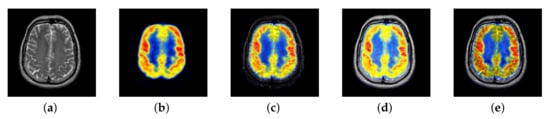

4.1.3. Subjective Evaluation Methods

Subjective evaluation methods generally rely on doctors in the field of organizing medical imaging to evaluate the visual effects of fused images. The evaluation method is relatively reliable. After all, the evaluation results are based on the doctors’ years of experience. However, there are also differences in the scores caused by the difference between the field of personal expertise and the research direction. The objective method predicts the visual quality of the fused image by modeling the human visual system, which can avoid the disadvantages of the subjective method. However, due to the complexity of the human visual system, modeling is impossible, so the evaluation result will deviate from human judgment. In our experiment, we used the above two methods to compare our algorithm with another seven representative algorithms. In order to minimize the interference of other factors on the subjective evaluation, we selected 10 male doctors and 10 female doctors in different hospitals, all of whom were from the medical imaging department. In order to reduce the impact of the environment on them, the assessment work is carried out in the same office. All images will be displayed on the computer monitor at the same resolution, so that you can ensure that everyone sees the same quality fused image. Scoring is done on a MATLAB GUI, which provides an enlarged tool for doctors to check details. The GUI is shown in Figure 5.

Figure 5.

Interface of subjective scoring system.

Doctors could give a score between 1 and 10 based on the texture, detail, and color changes in the fused image. For each fusion image, we will calculate its average score and variance as its subjective score. In view of the fact that there are three types of our functional images in the experiment, in the corresponding three types of fused images, we will select four groups of representative fused images for subjective scoring for each type.